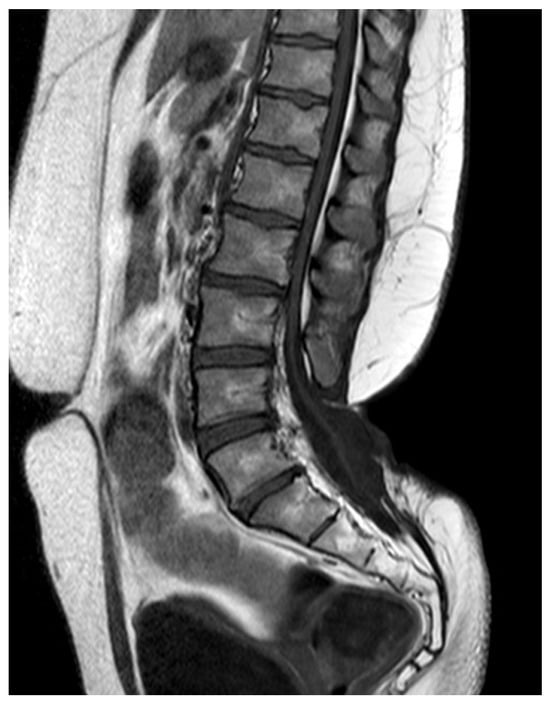

Figure 1. MR scan of a paediatric patient with three concomitant dermal tracts (white arrows). The conus is located at a physiological level L1.

In 13/52 (25%) cases there were two different dysraphic lesions. Two patients had three different dysraphic lesions (Figure 1). In total, there were 64 dysraphic lesions (Table 1): 22/64 (34.3%) conus lipomas (transitional in 13/22 (59%) cases, dorsal in 7/22 (31.8%) cases and chaotic in 2/22 (9%) cases); 13/64 (20.3%) dermal tracts; 12/64 (18.7%) LFTs; 5/64 (7.8%) SCMs; 3/64 (4.6%) agenesis of the conus as part of caudal regression syndrome; 2/64 (3.1%) LDM; 2/64 (3.1%) dermoid cysts; 2/64 (3.1%) presacral meningoceles as part of Currarino syndrome; 1/64 (1.5%) neurenteric cyst; 1/64 (1.5%) epithelialized MMC; and 1/64 (1.5%) meningocele.